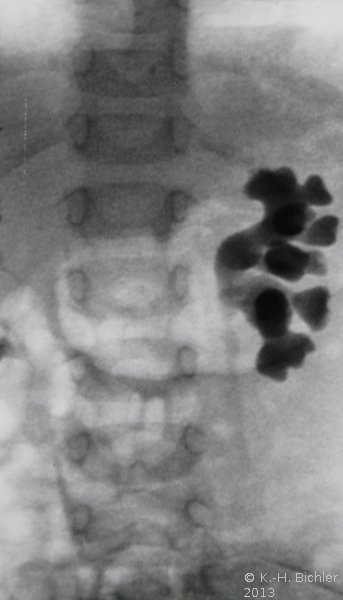

Bei dem 1 Jahre alten Mädchen fand sich bei rezidivierendem Harnwegsinfekt mit pyelonephritischen Veränderungen links und vesikoureteraler Reflux beiderseits ein Nierenbeckenstein links (

Abbildung 5abc). Im Infektfreien Intervall erfolgte die Stoßwellenbehandlung (

Abbildung 6).